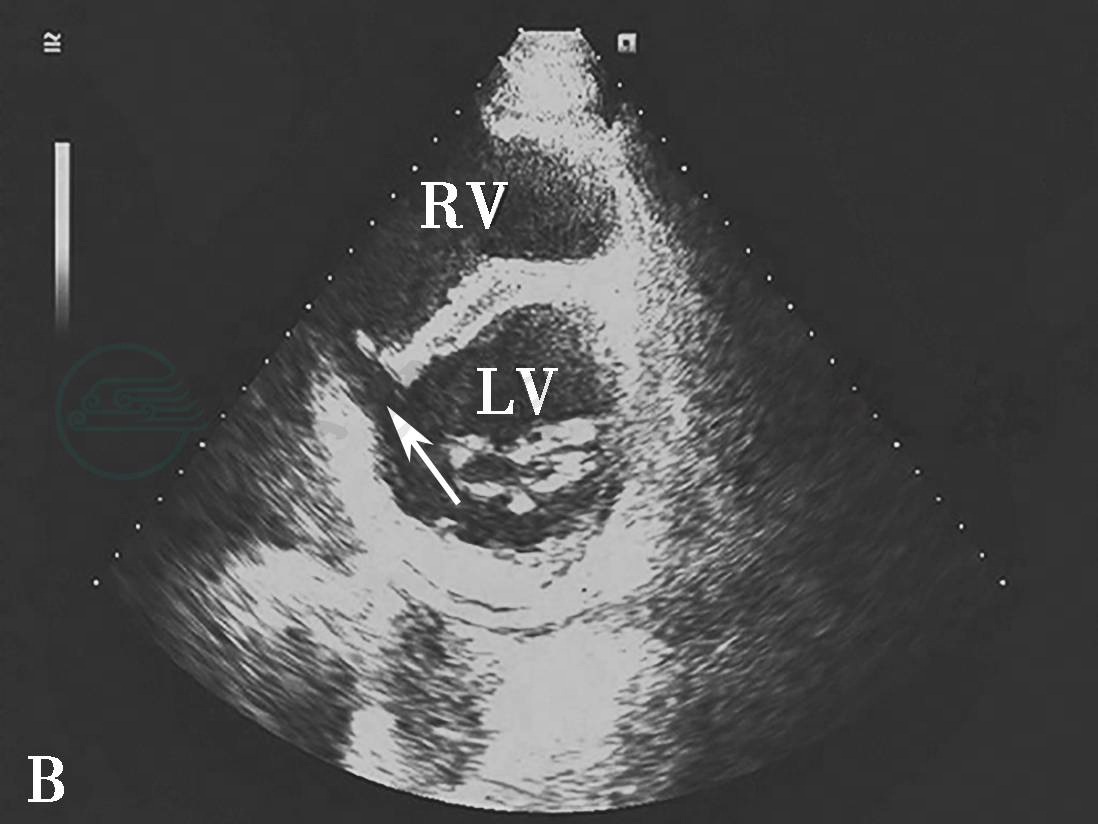

图4心肌梗死乳头肌断裂二维切面图像

心尖四腔心切面显示二尖瓣前外乳头肌部分断裂(虚箭头示)及乳头肌断端(实箭头示)。LA.左心房;LV.左心室。